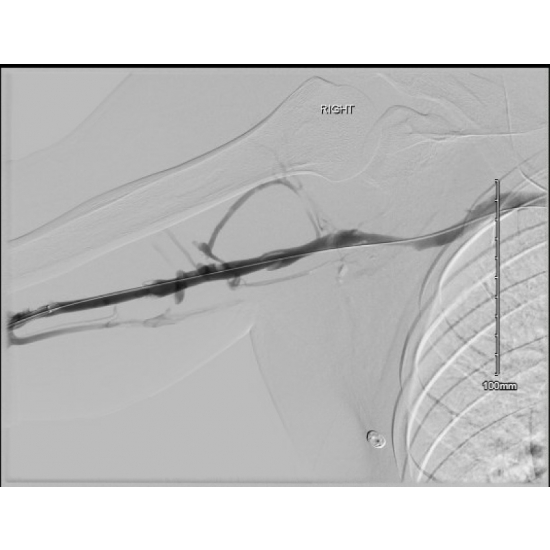

Peri-operative right upper extremity venogram demonstrated a complete occlusion of the right brachial, axillary, & subclavian veins. Large collateral from brachial to basilic vein, which appeared to drain the majority of the right upper extremity. Patent superior vena cava & right internal jugular.

BRACHIAL AND AXILLARY VEINS

Pre-Angio: NOTE COLLATERAL FLOW VIA PERFORATING VEINS FROM DEEP (BRACHIAL, AXILLARY, SUBCLAVIAN) TO SUPERFICIAL SYSTEM (IJ)